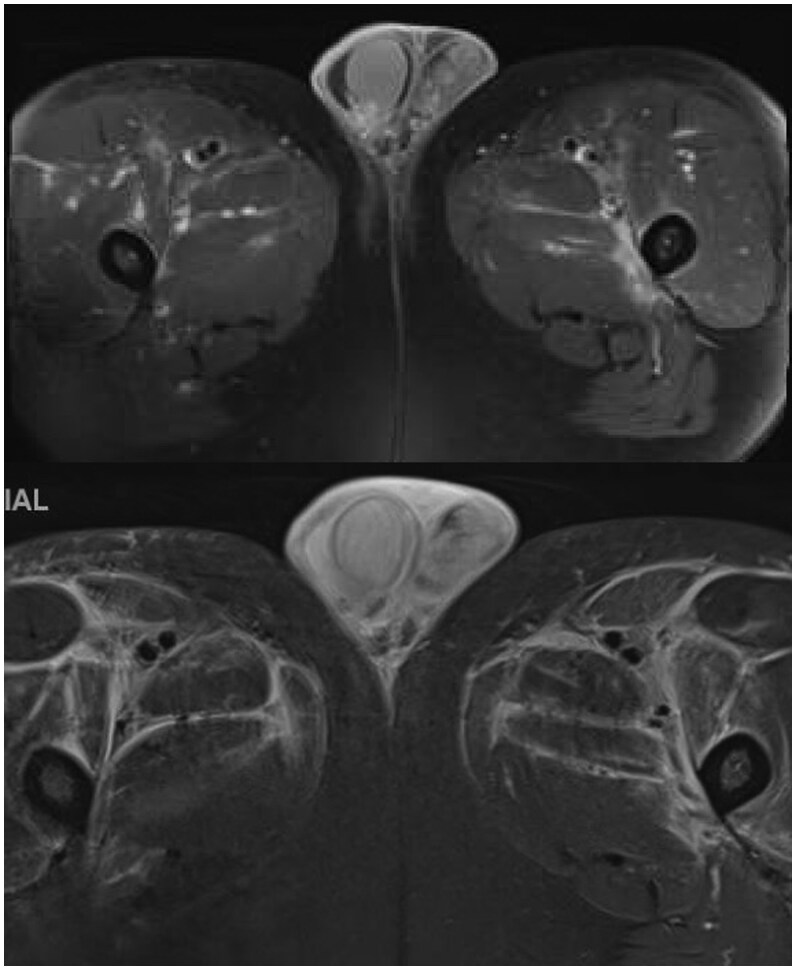

结节性多动脉炎(PAN)是一种全身性中小血管炎。它通常与乙型肝炎感染有关,典型表现为皮肤、胃肠道或神经系统受累。我们提出了一个病例56岁的男性谁提出了一个主诉的痛苦阴囊肿胀。最初的超声检查显示有附睾炎,患者开始使用适当的抗生素,但症状没有改善,因此入院。由于持续的阴囊疼痛、发烧和阴性的感染检查,F-18氟脱氧葡萄糖(FDG) PET/CT显示弥漫的高代谢活动贯穿中至小动脉血管,涉及血管炎。盆腔血管造影证实了诊断,患者开始使用类固醇并计划使用环磷酰胺。临床睾丸受累是一种罕见的PAN表现,尽管它经常在尸检中看到。以前报告的病例除了体质症状外,还表现出类似的阴囊疼痛和压痛,并使用类固醇和免疫抑制剂治疗。虽然组织病理学活检或血管造影通常是诊断PAN的金标准,但本病例也证明了F-18 FDG PET/CT在核医学诊断中的应用。结节性多动脉炎在F-18 FDG PET/CT上典型表现为中小血管的高代谢活动,最常见于下肢。由于类似的发现,本病例有助于报道核成像在诊断血管增生中的应用。

Polyarteritis nodosa (PAN) is a systemic small to medium vessel vasculitis. It is often associated with hepatitis B infection and classically presents with cutaneous, gastrointestinal, or nervous system involvement. We present a case of a 56-year-old male who presented with a chief complaint of painful scrotal swelling. Initial ultrasound demonstrated concern for epididymitis, and the patient was started on appropriate antibiotics without improvement of symptoms, resulting in admission. Due to continued scrotal pain, fevers, and negative infectious work-up, F-18 fluorodeoxyglucose (FDG) PET/CT was obtained, revealing diffuse hypermetabolic activity throughout the medium to small arterial vasculature, concerning for vasculitis. Abdominopelvic angiography confirmed the diagnosis, and the patient was started on steroids with plans to initiate cyclophosphamide. Clinical testicular involvement is a rare presentation of PAN, although it is often seen at autopsy. Previously reported cases have presented with similar scrotal pain and tenderness in addition to constitutional symptoms, as well as treatment with steroids and immunosuppressive agents. While biopsy with histopathology or angiography often serves as the gold standard for the diagnosis of PAN, this case also demonstrates the diagnostic utility of nuclear medicine with F-18 FDG PET/CT. Polyarteritis nodosa typically demonstrates hypermetabolic activity of the small- to medium-sized vasculature on F-18 FDG PET/CT, most often in the lower extremities. With similar findings, this case contributes to reports that show the utility of nuclear imaging in diagnosing vasculitides.